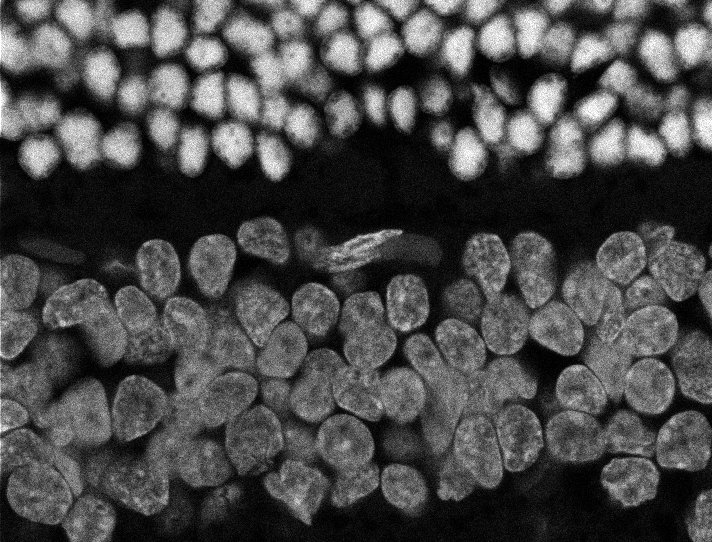

Nuclei